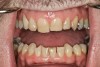

The teeth themselves often can be full of diagnostic information. Is there excessive tooth wear (Figure 7 through Figure 9)? Is there excessive mobility in any teeth? Is there unwanted migration of teeth? Is there a centric relation/maximum intercuspation discrepancy (hit on inclines and slide into full intercuspation) (Figure 3)? If there is a discrepancy, is the deviation in the arc of closure or line of closure? Is the patient able to chew all types of food on both sides without pain? Does the patient feel like their bite is changing or unstable? In addition, are there functional patterns evident by the wear present on the teeth. For instance, horizontal bruxers (Figure 10) often have flat tabletop wear present. Vertical, constricted wear patterns (Figure 11) often have anterior chipping and lingual wear of maxillary anterior teeth.

CLINICAL EXAMPLES (9.) Posterior dentinal exposure is a sign of occlusal instability; this exposure will only get worse if the cause is not resolved and the tooth restored. (10.) An example of a horizontal functioning patient; note the flat “table-top” wear patterns.

Figure 10  CLINICAL EXAMPLES An example of a horizontal functioning patient; note the flat "table-top" wear patterns.

Figure 10

Figure 11  CLINICAL EXAMPLES An example of a vertical wear patient; note the chipping and wear confined to the anterior teeth.

Figure 11